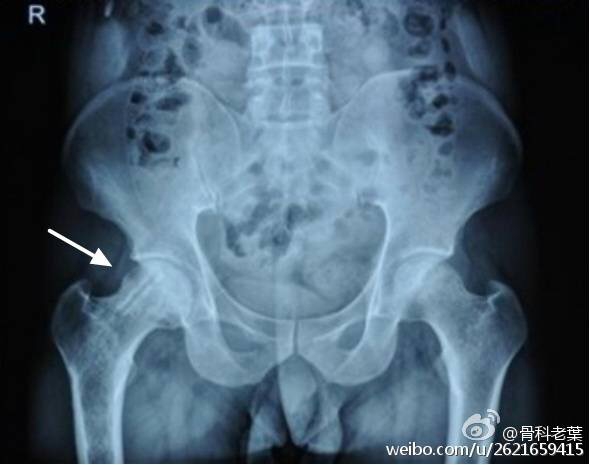

II期 病人有髋部症状,磁共振出现异常,X线片显示股骨头出现透光和硬化改变

III期 磁共振出现异常,X线片显示软骨下塌陷(新月征),股骨头内出现空洞,股骨头没有变扁

II期和III期的患者治疗方法相同,因为此时股骨头虽然还没有变形,暂时还不需要行人工关节置换术,但是股骨头已经出现空洞,随时股骨头就会塌陷变形,所以单纯的股骨头减压术是不能达到治疗效果的。这时就需要在股骨头减压的同时,植入一根支撑棒,顶住股骨头空洞区,防止股骨头在负重的情况下过早塌陷。其他治疗同之前相同,口服以上药物,定期复查,密切观察病情发展,尽量避免重体力劳动和爬山爬楼。

另附典型病例若干: